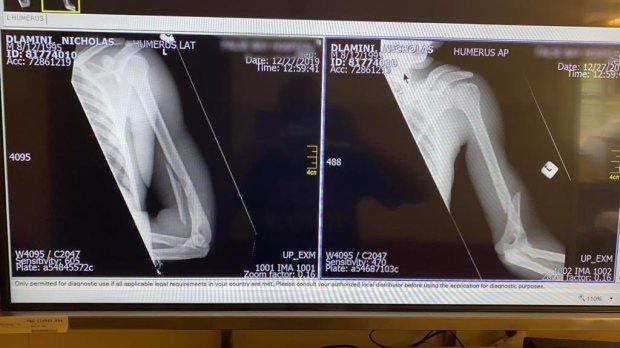

Lunes, 30 de diciembre – El equipo NTT Pro Cycling ha confirmado que el ciclista, Nic Dlamini, ha sido operado de su fractura de húmero. Además, se han conocido más datos sobre la actuación de los guardas quienes dijeron que no iban a actuar de manera violenta. Al parecer, dicha actuación vino motivada porque al ciclista sudafricano le exigían pagar una entrada la cual no había hecho efectiva al ingresar en el parque.

Actualización – El equipo NTT Pro Cycling ha confirmado, a través de un comunicado, la lesión de su corredor. Dlamini tiene una fractura en el húmero izquierdo y, en este momento, se encuentra en un hospital de Sudáfrica. Ahora, el ciclista sudafricano deberá recuperarse para una temporada que iba a ser bastante ilusionante con los JJOO como gran objetivo.

Su propio equipo ha anunciado que aún se le están haciendo pruebas, aunque desde fuentes cercanas al ciclista habría trascendido la siguiente radiografía.